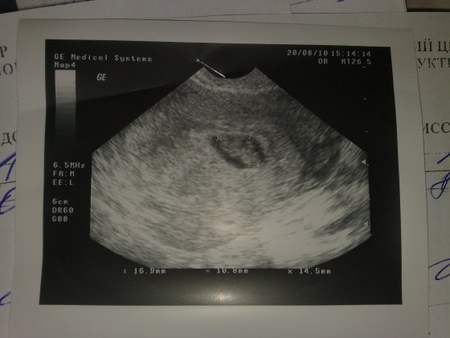

Фото УЗИ. Патология плодного яйца

Я в пятницу писала, что была на УЗИ. У меня 8 недель беременности. Врачи подозревают патологию плодного яйца. Я вставила фото УЗИ 6 недель и 8 недель. На них видно, что эмбрион вырос за две недели, а плодное яйцо не изменилось. УЗИст написал диагноз "Острое маловодие". Ничего не нашла в инете про такое на ранних сроках. Моя Г сказала, что возможно это из-за моего тироидита - это отклонения по эндокринологии, большое количество антител, происхождение которых врачи определить не могут ни у кого из пациентов с таким диагнозом. Я нашла хорошего врача гинеколога-эндокринолога, он полностью отмел это предположение, сказал, что тироидит никак не влияет ни на зачатие, ни на плод. В итоге врачи сошлись во мнении, что остается только ждать. Либо все нормализуется (но сказали, что мало шансов), либо прерывание беременности. Сказали, что не стоит пытаться сохранить ее во что бы то ни стало. Следующее УЗИ назначили на среду. Каждый день для меня длится целую вечность.